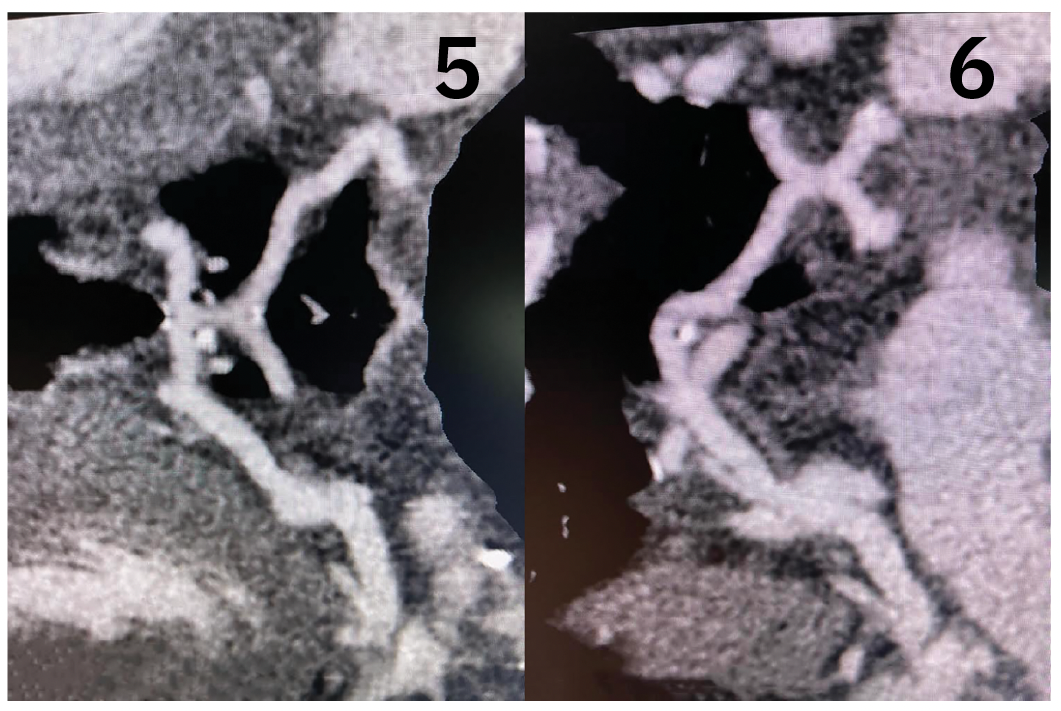

Consequently, she underwent cardiothoracic surgery, during which the left main coronary artery was ligated at the level of the pulmonary artery, and a left internal mammary artery (LIMA) was used to bypass the left anterior descending artery and a reverse saphenous vein graft was used to bypass the obtuse marginal artery. A patch reconstruction was performed on the pulmonary artery (Figures 5-6).

The patient recovered well from surgery with no complications. Transthoracic echocardiogram showed recovery of her left ventricular ejection fraction to within normal limits. Serial CCTA scans showed a widely patent LIMA graft to the left anterior descending artery seven years post surgery.

Complications of this procedure include stenosis of saphenous vein and arterial grafts, as well as a high percentage of redo procedures, more commonly in vein grafts. In our case, the procedure was successful with no complications. Coronary CTA seven years post surgery showed patent anastomosis without significant narrowing, indicating excellent long-term results of the LIMA graft and ligation ALCAPA repair in an adult. The saphenous vein graft to obtuse marginal graft remained patent as well.